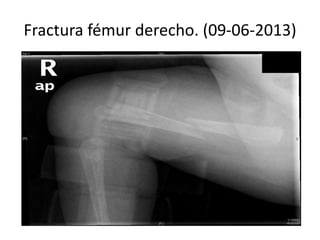

Fractura fémur derecho. (09-06-2013)

• 09-06-2013 ( 1,5 mes)fractura espontánea de

fémur derecho ( en brazos de su madre)